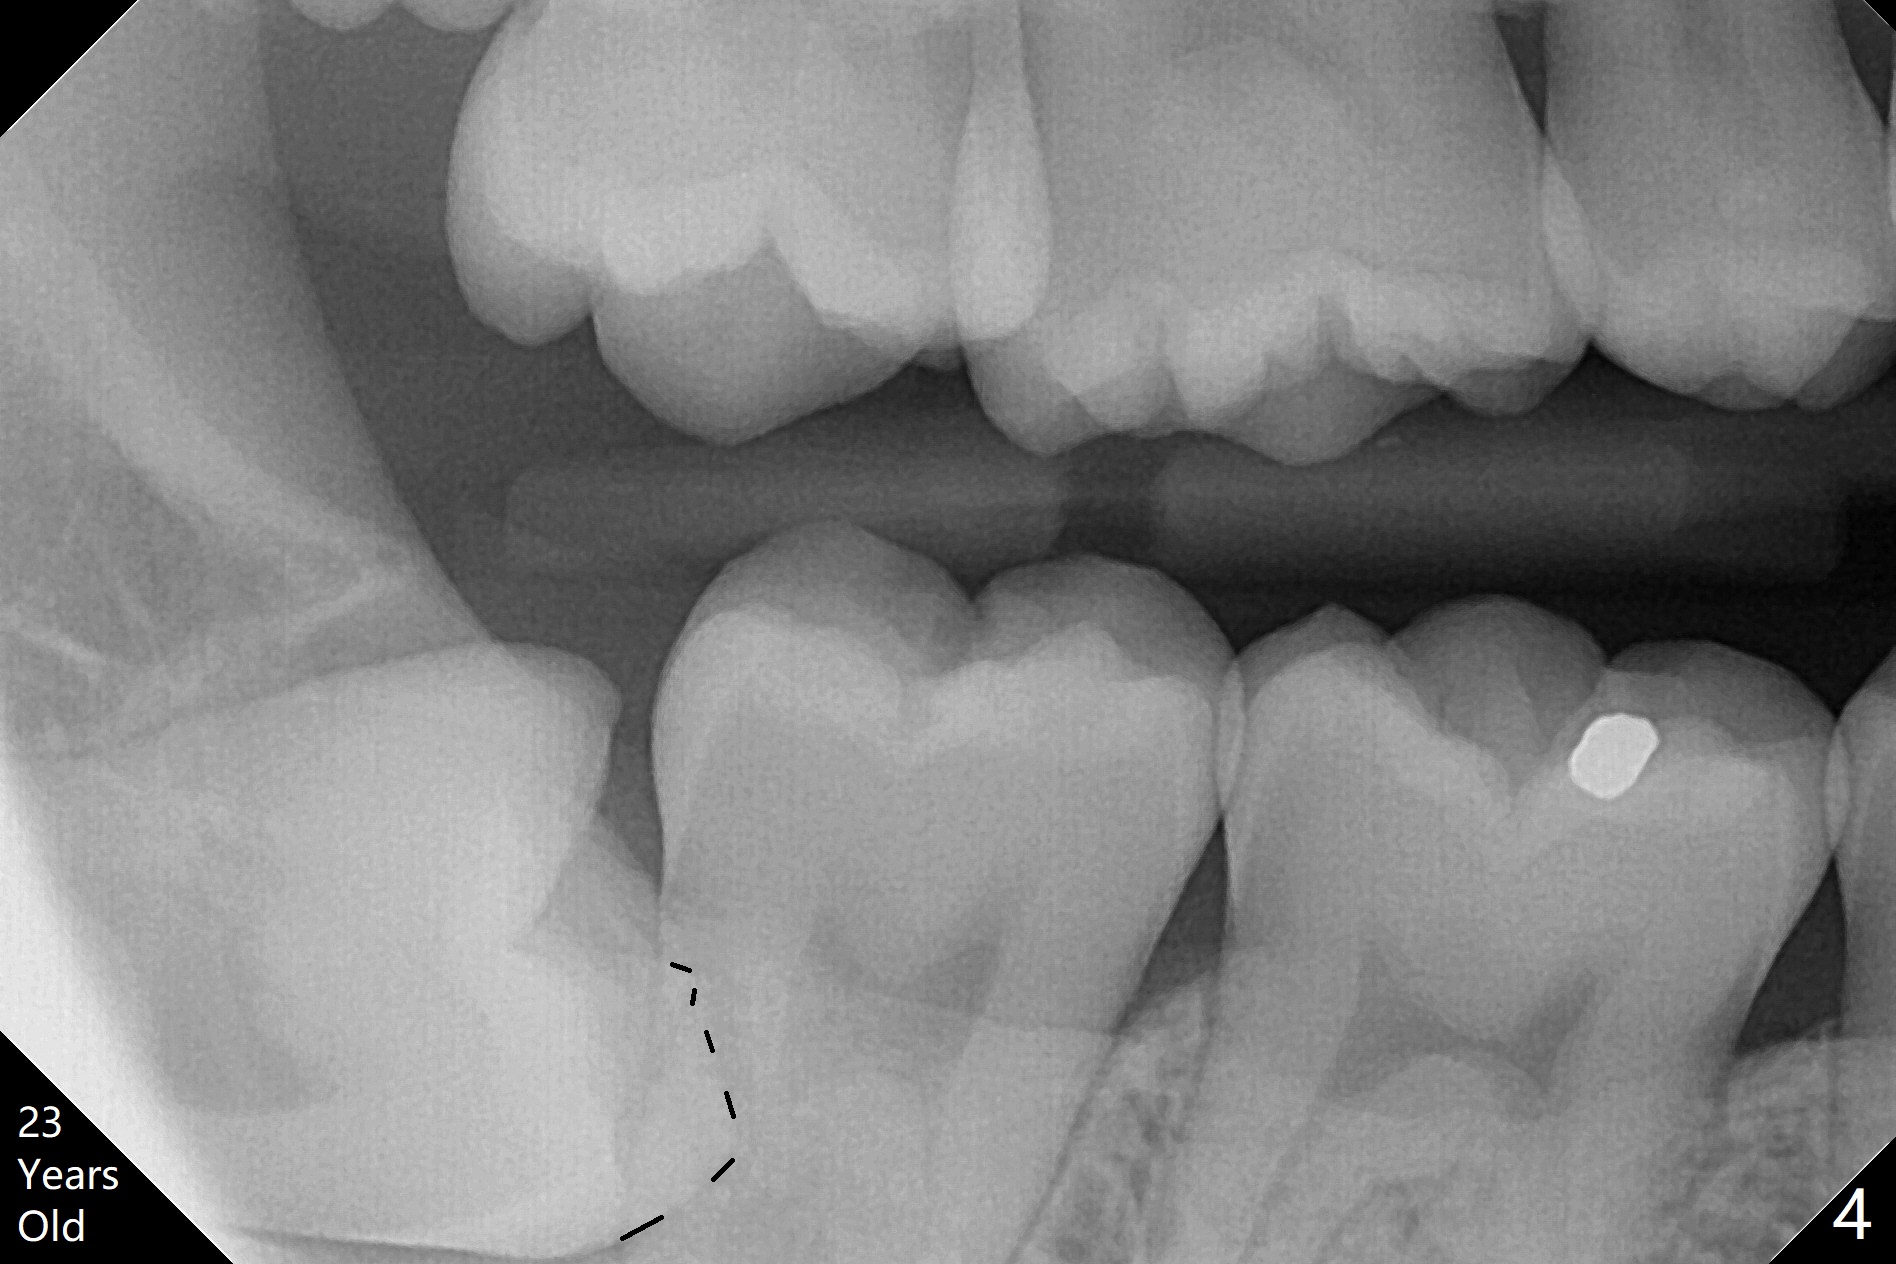

A 25-year-old woman, under our care for the last 11 years (Fig.1-6), returns for #1 and 32 extraction (1 year after #16 and 17 extraction (Osteogen plug)). Preop PA shows that a portion of the lower impacted tooth may be located buccal to the tooth #31 (Fig.4 black dashed line). An accessory incision is moved from distobuccal to midbuccal (Fig.7 arrowheads) to reduce postop loss of bone graft (Fig.8 B) from the incision. In fact the incision should be further moved to mesiobuccal (Fig.9 red line) if buccal impaction is suspected (curved black line). The buccal impaction of #32 of her father is more severe.